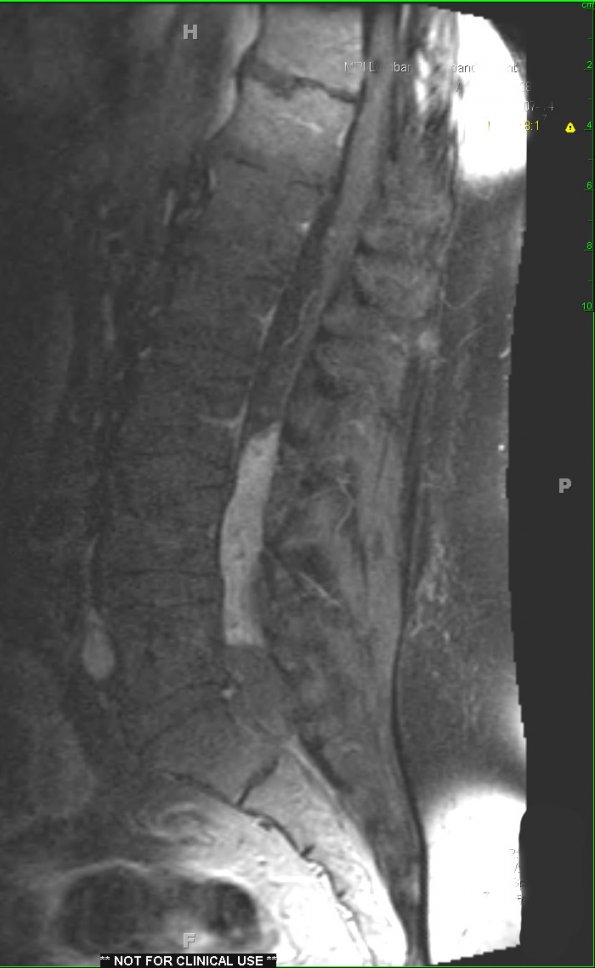

MRI examination shows a boxcar shaped mass as viewed with T1-weighted scan with contrast (17A2) and T2-weighted scans.